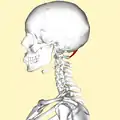

Position of rectus capitis posterior minor muscle (shown in red). Animation. Lateral view of human skull (rectus capitis posterior minor shown in red.)

Lateral view of human skull (rectus capitis posterior minor shown in red.) Occipital bone. Outer surface.